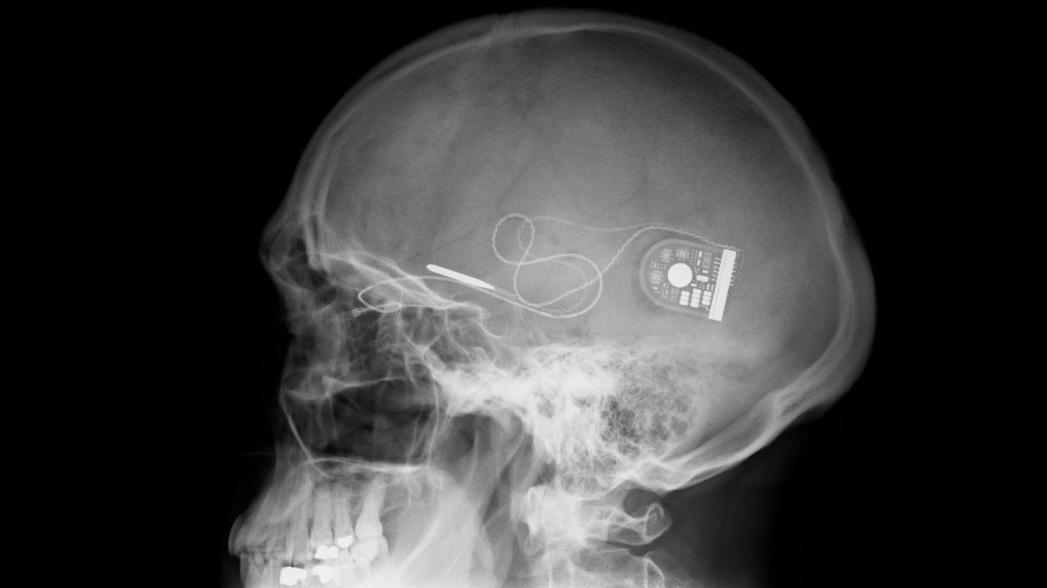

Кохлеарные имплантаты

Кохлеарный имплантат — медицинский прибор, протез, позволяющий компенсировать потерю слуха некоторым пациентам с выраженной или тяжёлой степенью нейросенсорной тугоухости, которые не могут использовать обычный слуховой аппарат.

Сущность метода заключается в установке в организме пациента устройства, способного преобразовывать электрические импульсы, поступающие с внешнего микрофона, в сигналы, понятные нервной системе. При этом под кожей (в височной области) устанавливается тело имплантата, а через барабанную полость в барабанную лестницу ушной улитки проводится электродный массив.

HiRes Ultra 3D компании Advanced Bionics

Кохлеарный имплантат HiRes Ultra 3D не доставляет неудобств или боли своим пользователям и является хорошим выбором для пациентов, которым может понадобиться пройти МРТ-обследование.

Инновационный мультимагнитный блок Ultra 3D совместим с магнитным полем любого МРТ-сканера независимо от ориентации пациента и его движения. Это позволяет взрослым и детям, использующим кохлеарный имплантат, безопасно проходить процедуру МРТ-сканирования высокого разрешения, без хирургического вмешательства или перевязки головы, не испытывая боли или дискомфорта, и без ограничений в ориентации головы во время процедуры МРТ.

Напомним, что взаимодействия магнитного поля от аппаратов МРТ с магнитом имплантата внутри головы вызывало головокружение и последующую боль. Новая мультимагнитная технология Advanced Bionics рассчитанf на многократное воздействие МРТ-процедур без потери магнитной прочности или подвижности компонентов магнитного блока.

Этот кохлеарный имплант был удостоен награды MedTech Breakthrough Award 2019 как лучшее комплексное решение в области медицинского оборудования.